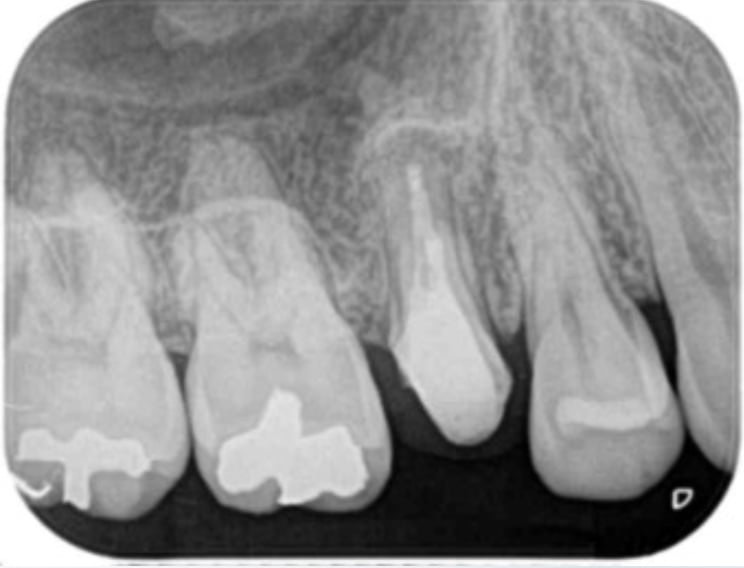

A comparison of survival of teeth following endodontic treatment performed by general dentists or by specialists

Bradley S Alley, DMD, G Gray Kitchens, DMD, Larry W Alley, DMD, Paul D Eleazer, DDS, MS

Oral Surgery,Oral Medicine,Oral Pathology,Oral Radiology,and Endodontology Volume 98, Issue 1, July 2004, Pages 115-118